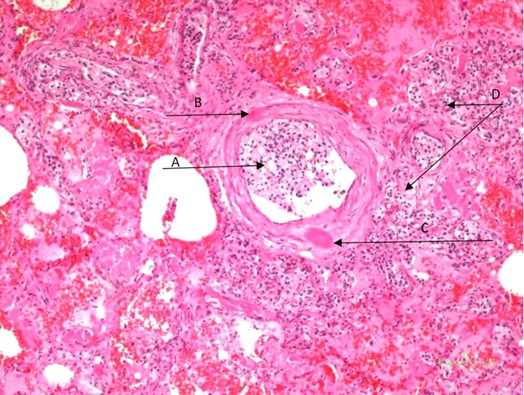

Pulmonary Lymphangitic Carcinomatosis of Small Cell Lung Carcinoma: An Autopsy Case Report

Ronniel Morais Albuquerque, Gabriela Naccarati de Mello, Maria Clara Nascimento Lopes, Murilo Lima Gomes, Amaro Nunes Duarte Neto

bjcr119